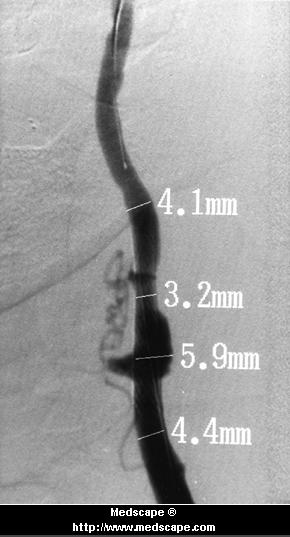

carotid stenosis before (arrows) and after PTCA/stent